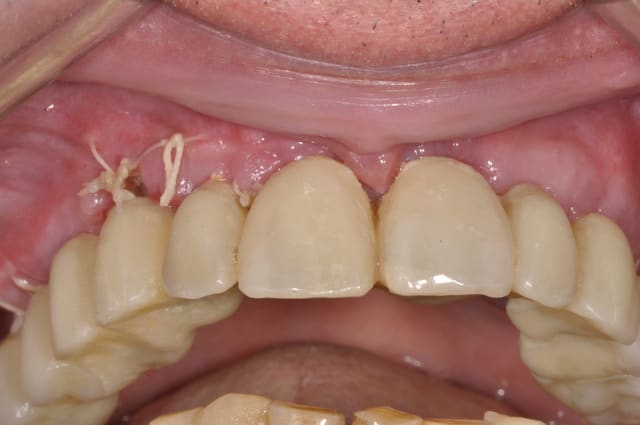

les contrôles à 7 jours, 2 photos par cas

amusez vous à les reconnaitre!

Comme cette technique semble vous passionner, je mets un cas en photos:-))

Pour 3000€ de plus je posais un optragate! C'est le patient qui n'a pas voulu!!!!!!!!!!!!!!!!!!!